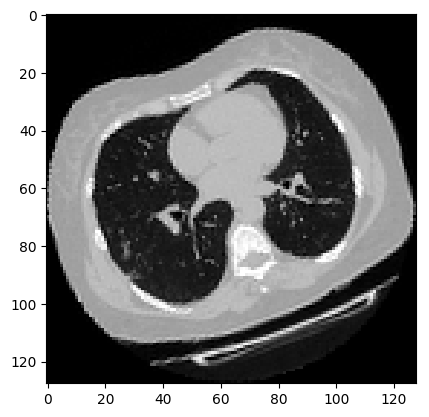

可视化增强型 CT 扫描。

[11]:

images, labels = train_dataset.__getitem__(0)

print(images.shape)

image = np.squeeze(images, 3)

print("Dimension of the CT scan is:", image.shape)

plt.imshow(np.squeeze(image[:, :, 30]), cmap="gray")

plt.show()

(128, 128, 64, 1)

Dimension of the CT scan is: (128, 128, 64)

../../_images/practices_cv_3D_image_classification_from_CT_scans_18_1.png

由于CT扫描有许多层切片,可视化多层切片。